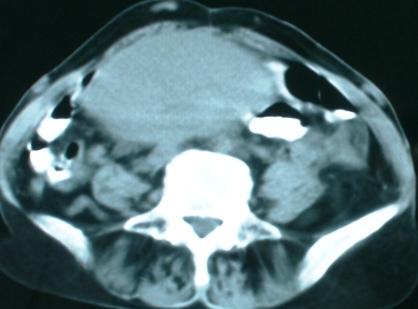

以下是引用zsl6918在2008-11-4 19:14:00的发言:[br]多发转移性改变,子宫改变不除外为原发灶